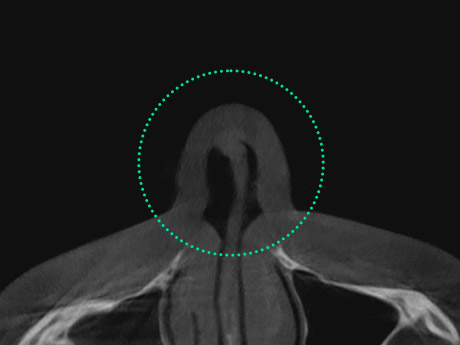

Crooked Nose Surgery is a procedure to straighten a deviated nose

caused by structural internal issues or trauma leading to asymmetry

of the bone or cartilage. Depending on the severity of the deviation,

a crooked nose can affect breathing, causing discomfort. Through

3D-CT scans, it is determined whether the deviation stems from

internal cartilage or is simply an external appearance issue. Accurate

diagnosis is essential, followed by a customized surgical approach

to properly correct the condition.

Nasal Valve Stenosis

The nasal valve, located at the upper part

of the internal nose, regulates airflow.

When the septal cartilage is bent, it narrows

this passage, resulting in breathing difficulties and

nasal obstruction. This condition, known as nasal

valve stenosis, is more common in individuals

with a low nasal bridge.

Narrowing of the upper internal nasal area,

responsible for regulating airflow, leads to nasal

obstruction and sleep disorders.

Plastic Surgery and

ENT Specialists

Collaboration System

VIEW Plastic Surgery offers a collaborative

system between

plastic surgeons and

ENT specialists. Through 3D-CT and

endoscopic

diagnosis, we address discomfort caused by

nasal conditions such as nasal congestion,

rhinitis, and

sinusitis, while refining the nose line

to create a more defined

and harmonious

appearance.

Establish a Surgical Plan

after

a Precise Examination

of the

Internal Nasal

Structure and

Tissue

Condition

Using nasal

Endoscopy and

3D-CT

Through detailed examinations of the internal

nasal structure

and tissue using 3D-CT and

endoscopy, we accurately

diagnose hidden

issues. Based on these findings,

we identify

the exact causes and develop a

personalized 1:1 surgical plan

tailored to each

patient.